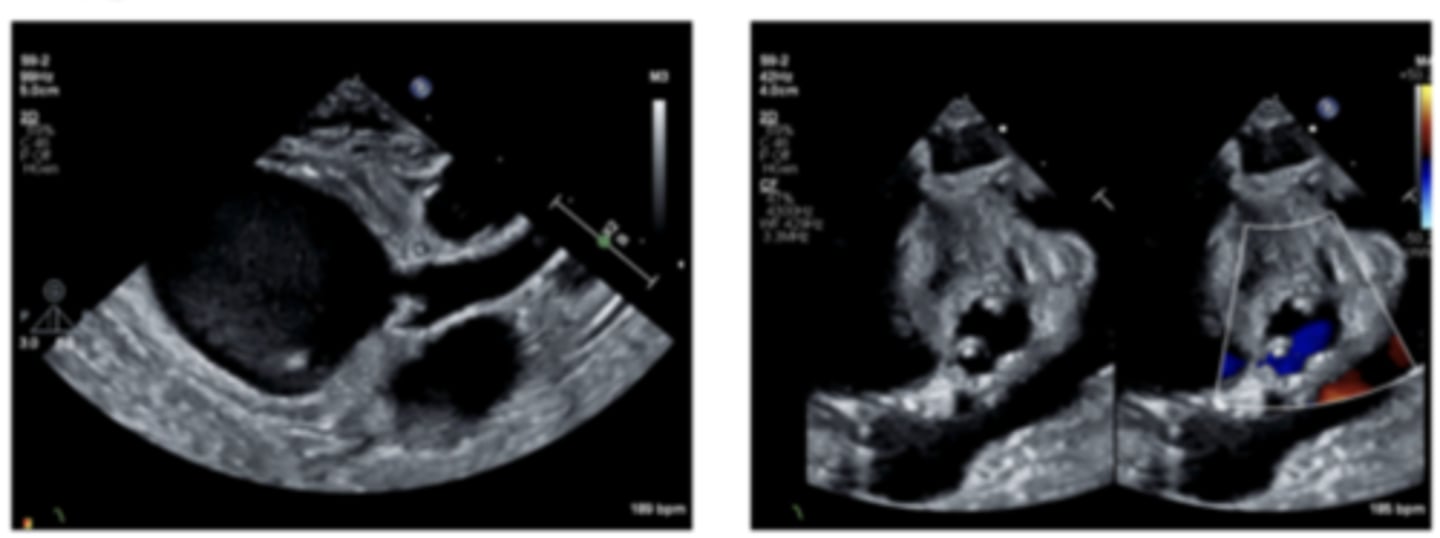

Interrupted Aortic Arch (IAA)

WHAT LESION?